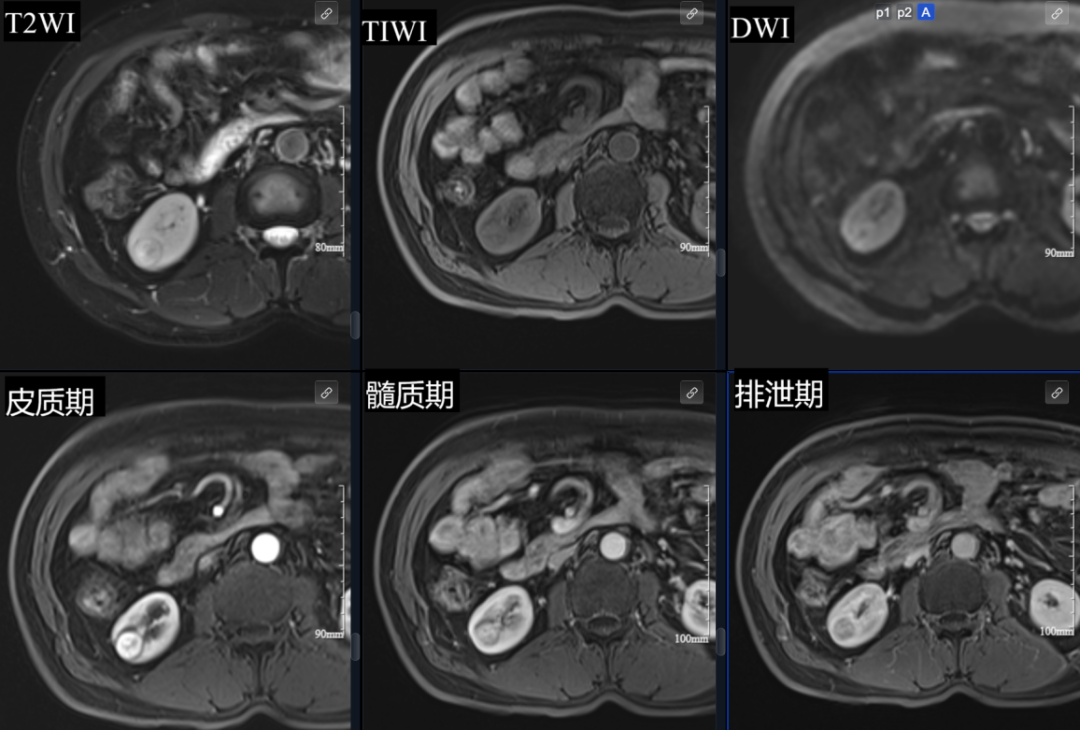

基于这一研判,我机构内部绿色通道迅速开启。叶先生在当天(11 月 10 日)就完成了肾脏增强 MRI 检查。

增强影像清晰显示:右肾下极混杂信号结节影较前增大,考虑肾癌可能。这一诊断也与超声结果相互印证。从发现异常到明确诊断,全程不超过 24 小时。

得益于 24 小时确诊: 临床医生在第一时间就获得了「考虑肾癌」的明确影像诊断。这为叶先生赢得了宝贵的诊断时间窗口,使他能够立即进入临床诊疗阶段,为接受可能的早期肾癌根治性手术(如保肾手术)创造了最佳条件,极大提升了治愈率和生存质量。